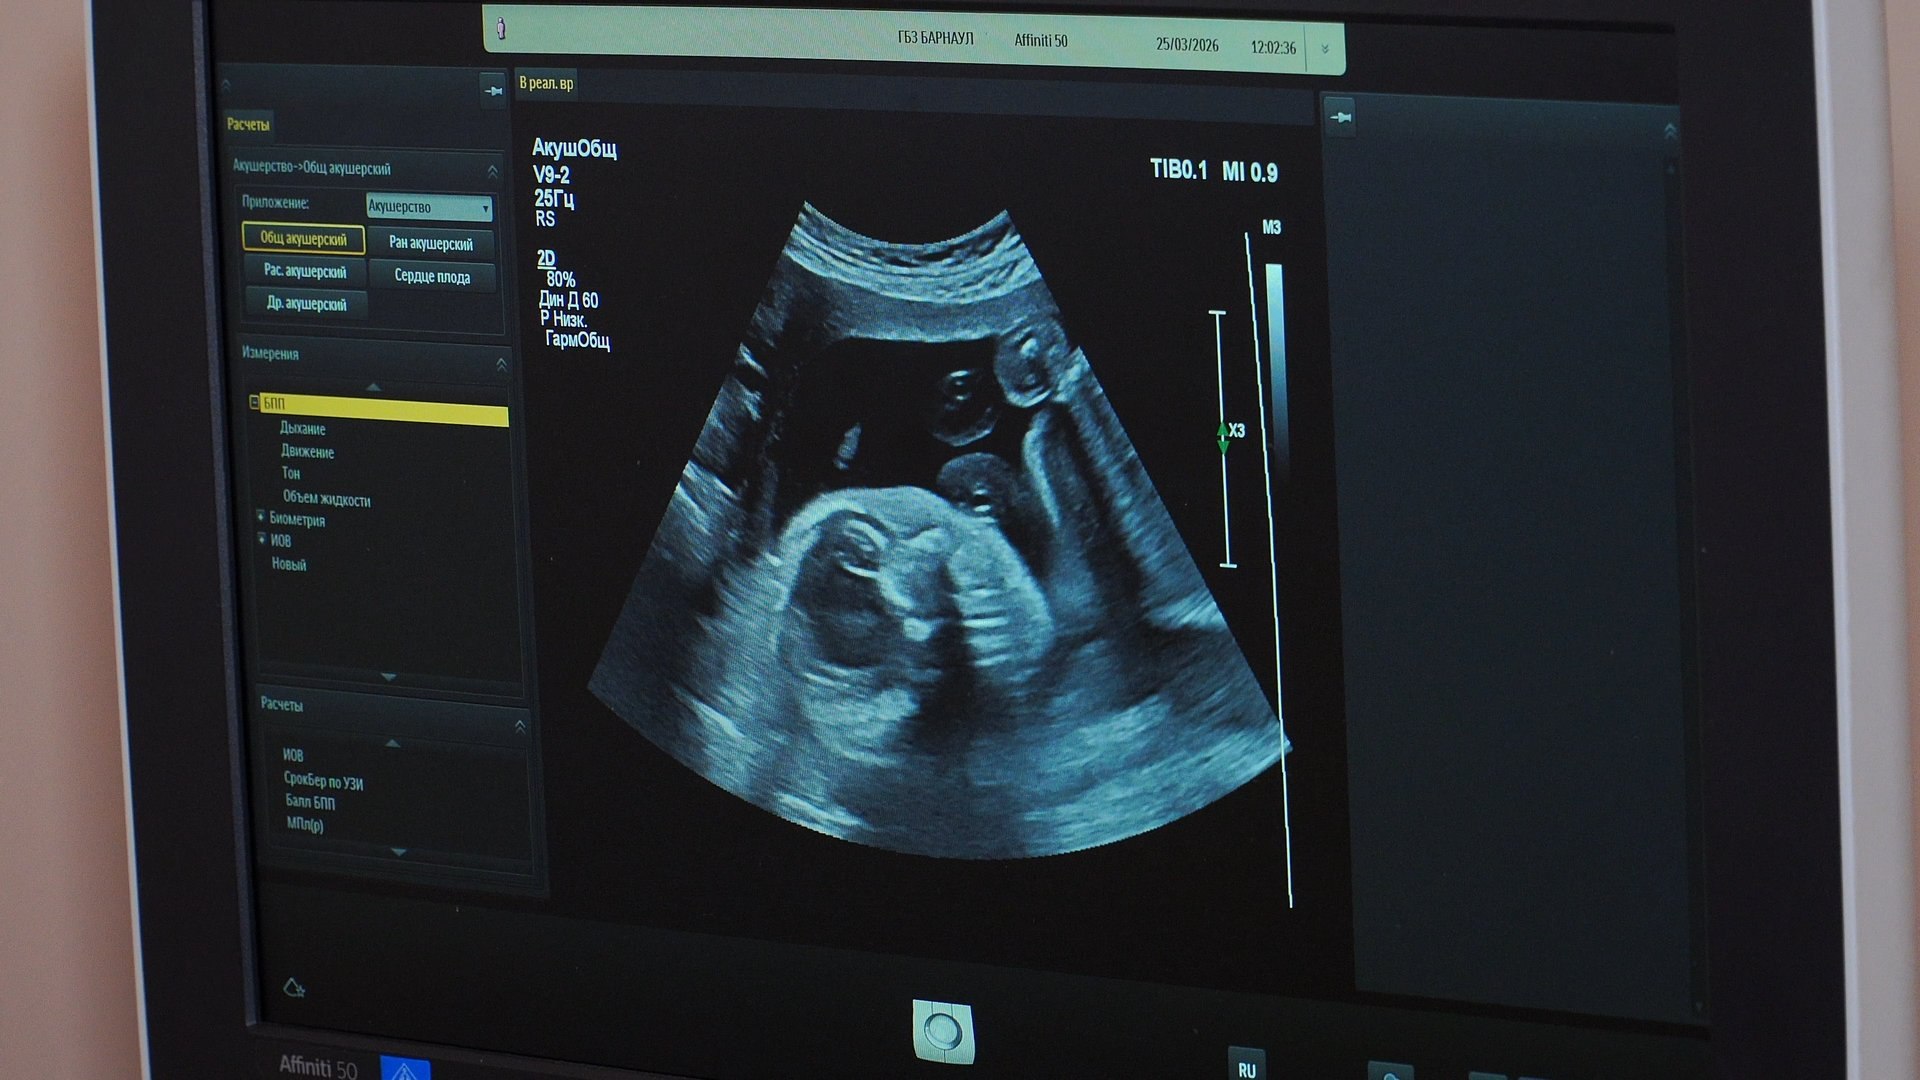

Рожать с рубцом на матке — огромный риск, который может обернуться разрывом во время естественных родов. Но врачи барнаульской больницы № 3 помогают благополучно перенести такую сложную беременность.

Сегодня в женской консультации этой больницы наблюдаются больше 350 пациенток. Медики отмечают: средний возраст первых родов в Барнауле снизился до 25 лет. Чтобы подготовить девушек, при медучреждении уже четыре года работает бесплатная школа. Там на практике показывают, как правильно дышать в родах, пеленать малыша и ухаживать за ним.